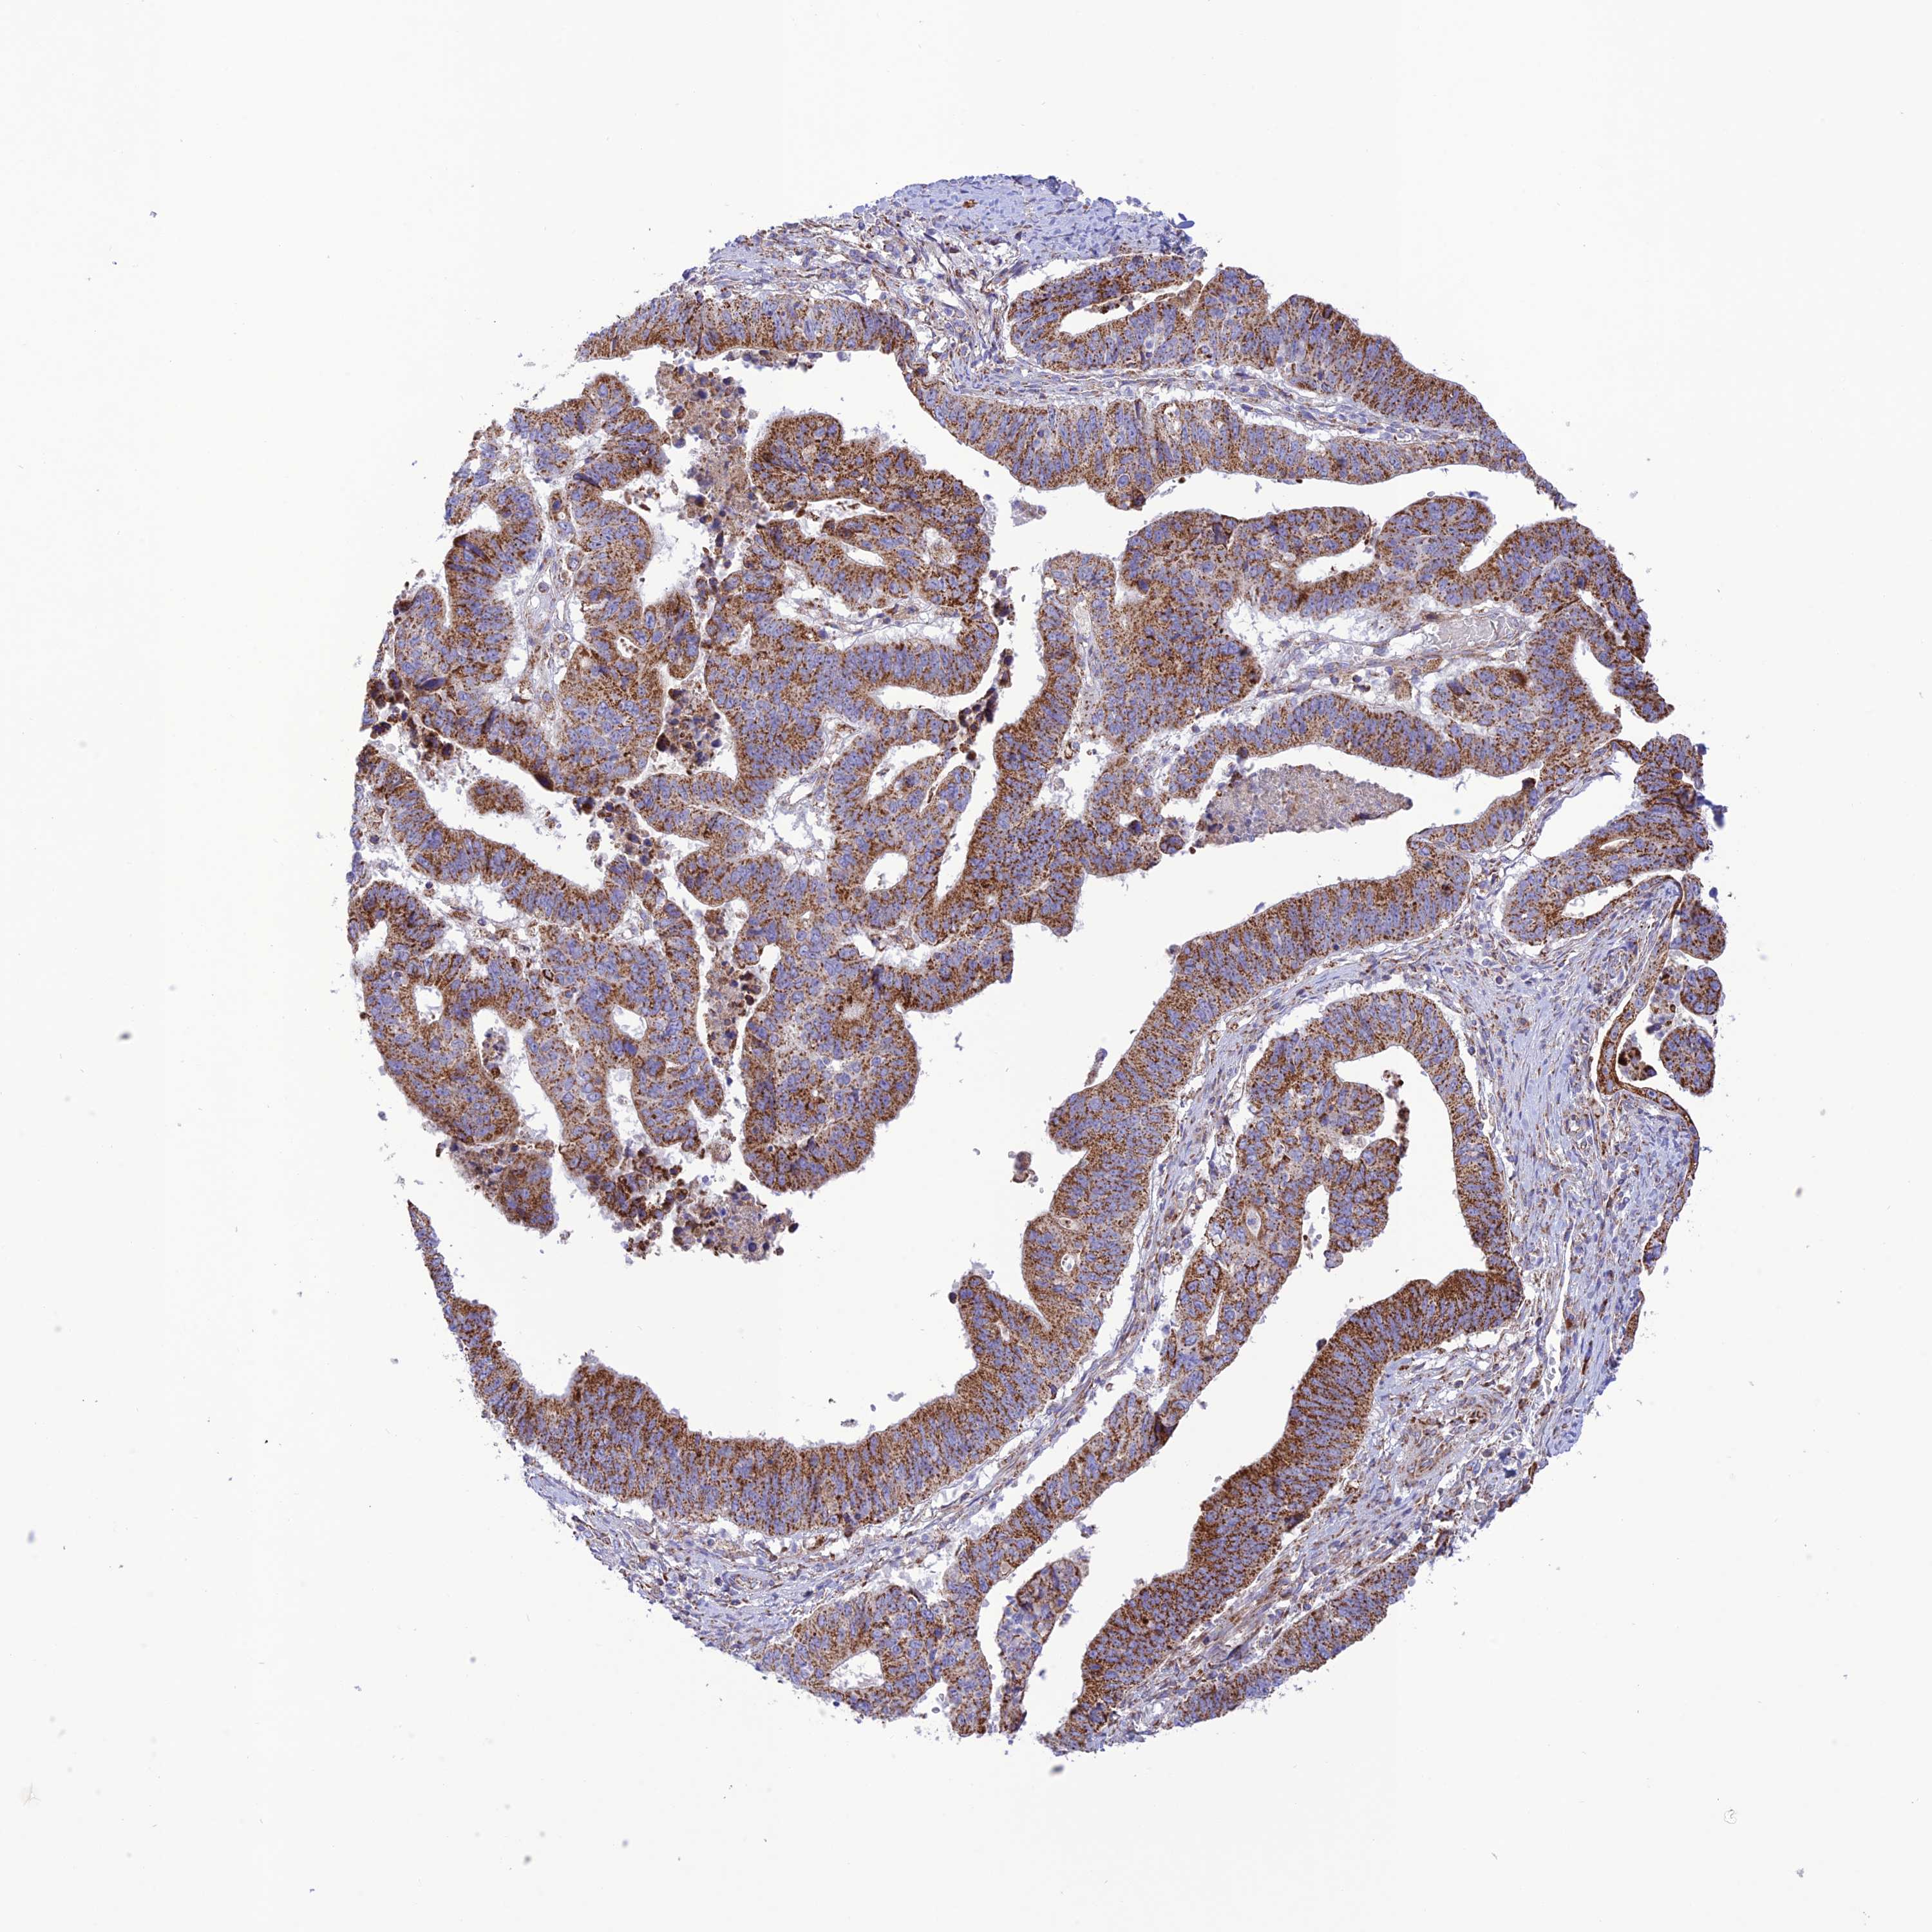

STOMACH CANCER - Protein expressioni

A mouse-over function shows sample information and annotation data. Click on an image to view it in a full screen mode. Samples can be filtered based on level of antibody staining by selecting one or several of the following categories: high, medium, low and not detected. The assay and annotation is described here.

Note that samples used for immunohistochemistry by the Human Protein Atlas do not correspond to samples in the TCGA dataset.

Antibody stainingi

Antibody staining in the annotated cell types in the current human tissue is reported as not detected, low, medium, or high, based on conventional immunohistochemistry profiling in selected tissues. This score is based on the combination of the staining intensity and fraction of stained cells.

Each image is clickable and will lead to virtual microscopy that enables deeper exploration of all samples and also displays staining intensity scores, fraction scores and subcellular localization as well as patient and tissue information for each sample.

Antibody HPA044356

Staining

High

Medium

Low

Not detected

Intensity

Strong

Moderate

Weak

Negative

Quantity

>75%

75%-25%

<25%

None

Location

Nuclear

Cytoplasmic/membranous

Cytoplasmic/membranous,nuclear

Adenocarcinoma, NOS